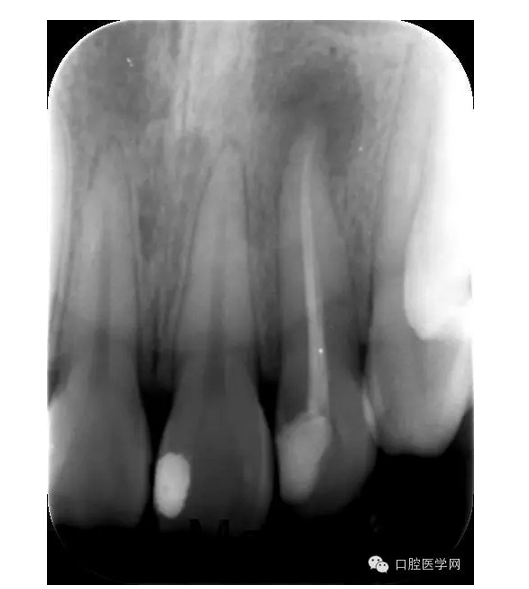

X線片:示22已行根管治療,治療不完善,根尖區(qū)可見約0.5*0.5mm密度減低區(qū),牙周膜影略增寬。

診斷:22急性根尖周炎

治療:第一次:去舊充填體,去腐質(zhì),GG鉆去除牙膠充填體,疏通根管,測量工作長短,H銼與K銼去除剩余牙膠,雙氧水和鹽水大量沖洗,機擴至S1,超聲蕩洗,激光行根管消毒,封CP球。